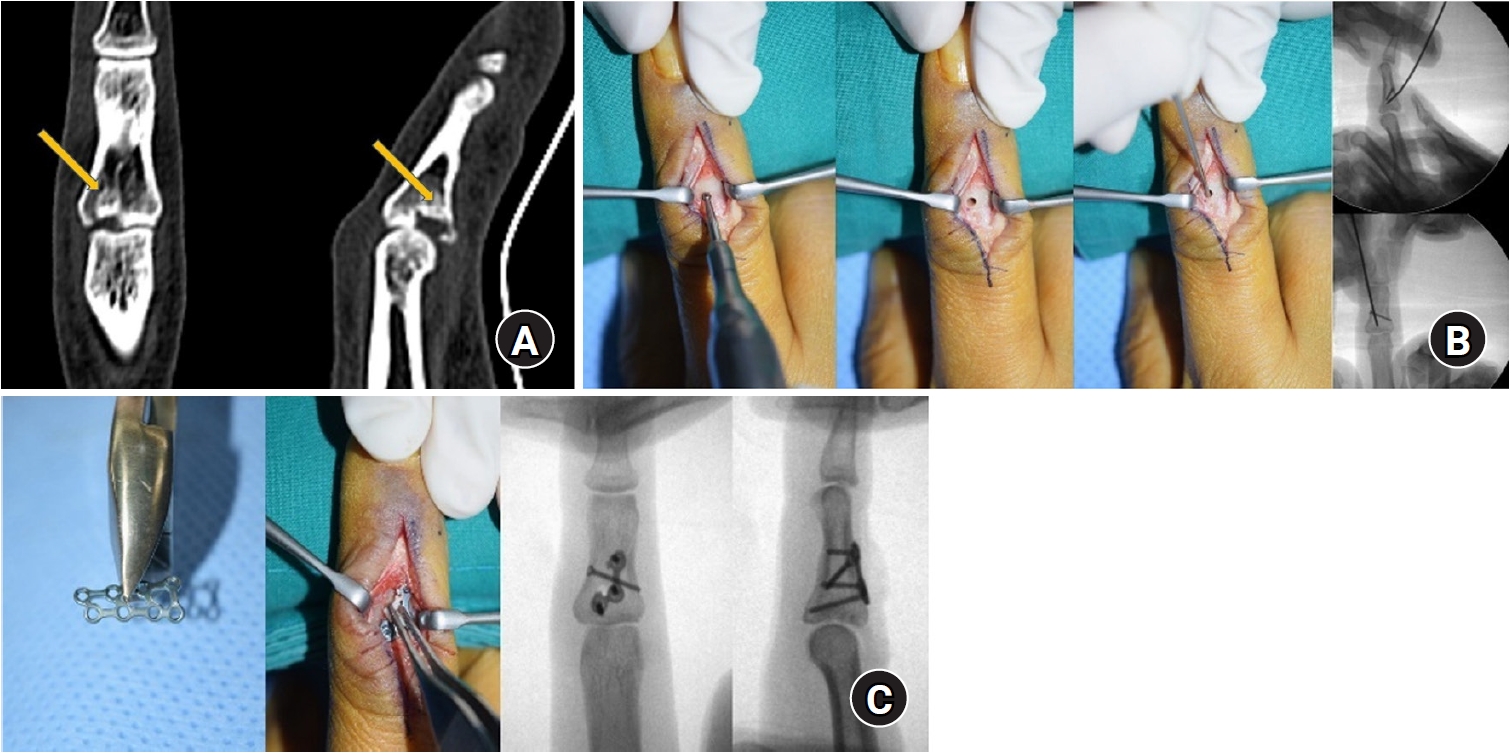

Pilon-type fractures occur due to axial compression, leading to intraarticular fragment depression and, additionally, the separation and displacement of volar or dorsal fragments. Instability primarily increases during extension. Given the comminuted nature and displacement of intraarticular fragments, many of these fractures require surgical treatment, which is generally more challenging than other types of fracture displacement [9]. A surgical approach often involves a volar approach to expose the entire base of the proximal phalanx by opening the joint capsule and fully hyperextending the PIP joint to 180° (shotgun approach), though this may result in increased soft tissue dissection. In cases where fracture displacement is not severe, closed reduction and K-wire fixation may be attempted. The depressed articular fragments can be reduced into the proximal phalanx and secured with subsequent K-wires (Fig. 6). Recently, Park et al. [53] reported good outcomes with a technique that does not require joint exposure, in which an extraarticular cortical window is created to perform trans-osseous reduction of the depressed intraarticular fragments, followed by fixation with low-profile locking plates (Fig. 7). This technique results in less soft tissue dissection compared to a volar approach and facilitates easier reduction of the articular fragments, ultimately enabling early joint mobilization through locking plate fixation.

Fig. 6.

Closed reduction and K-wire fixation for depressed articular fragment and dorsal subluxation. In lateral C-arm image intensifier, middle phalanx articular fragment depressed and dorsal joint subluxation was identified (A). With extension blocking pin inserted, the depressed joint fragment reduced using intramedullary K-wire by closed method (B). Additional inter-fragment K-wire inserted from dorsal aspect in properly reduced position (C). Finally, additional volar flexion blocking pin was inserted (D).

Fig. 7.

A representative case of trans-osseous reduction and dorsal locking plate fixation. A preoperative computed tomography scan presented a volar lip fracture with a depressed intra-articular fragment (arrows) (A). Cortical window creation on the dorsal bare area of the middle phalanx, and reduction of the impacted fragment using a Kirschner-wire inserted through the window (B). Locking plate positioning after reduction and insertion of the most proximal screw to buttress the articular fragment (C). Case courtesy of JW Park from Korea University, Seoul, Korea.

Fig. 6. Closed reduction and K-wire fixation for depressed articular fragment and dorsal subluxation. In lateral C-arm image intensifier, middle phalanx articular fragment depressed and dorsal joint subluxation was identified (A). With extension blocking pin inserted, the depressed joint fragment reduced using intramedullary K-wire by closed method (B). Additional inter-fragment K-wire inserted from dorsal aspect in properly reduced position (C). Finally, additional volar flexion blocking pin was inserted (D).

Fig. 7. A representative case of trans-osseous reduction and dorsal locking plate fixation. A preoperative computed tomography scan presented a volar lip fracture with a depressed intra-articular fragment (arrows) (A). Cortical window creation on the dorsal bare area of the middle phalanx, and reduction of the impacted fragment using a Kirschner-wire inserted through the window (B). Locking plate positioning after reduction and insertion of the most proximal screw to buttress the articular fragment (C). Case courtesy of JW Park from Korea University, Seoul, Korea.